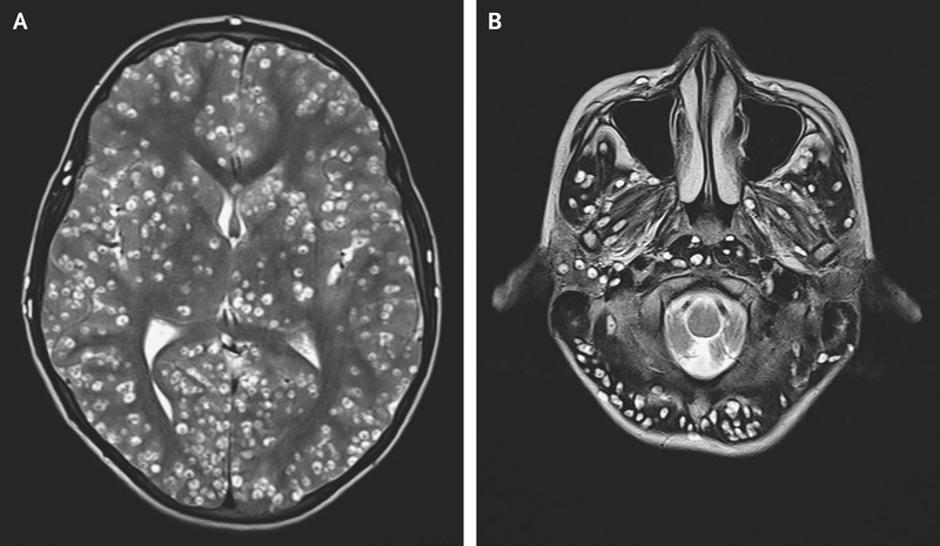

Magnetna resonanca možganov je pokazala na ciste po vseh delih možganov ( na slikaj spodaj kot bele pike). Okusen obrok svinjskega mesa je v njegovem črevesju spodbudil razvoj trakulje, ki je potovala vse do njenih možganov. Tam je odložila svoje ličinke, zaradi katerih pa so njegovo glavo dobesedno preplavile ogromne ciste.

| Avtor: BMJ BMJ

Fant je trpel za hudo obliko nevrocisticerkoze, eno izmed parazitskih bolezni, ki jo pri človeku povzročajo ličinke svinjske trakulje. Je najpogostejša parazitska okužba osrednjega živčevja in je lahko tudi glavni vzrok epilepsije. Ljudje s okužijo zaradi jajčec svinjske trakulje v ne dovolj kuhani svinjini in v hrani kontaminirani s človeškim urinom ali iztrebki.

Huda oblika parenhimske nevrocisticerkoze je cisticerkozni encefalitis, pri katerem je možganovina okužena s številnimi cisticerki, ki izzovejo močan vnetni odgovor. Klinični zanki so podobni drugim akutnim encefalitisom. Bolniki imajo lahko motnje zavesti, oslabljen vid in generalizirane krče.